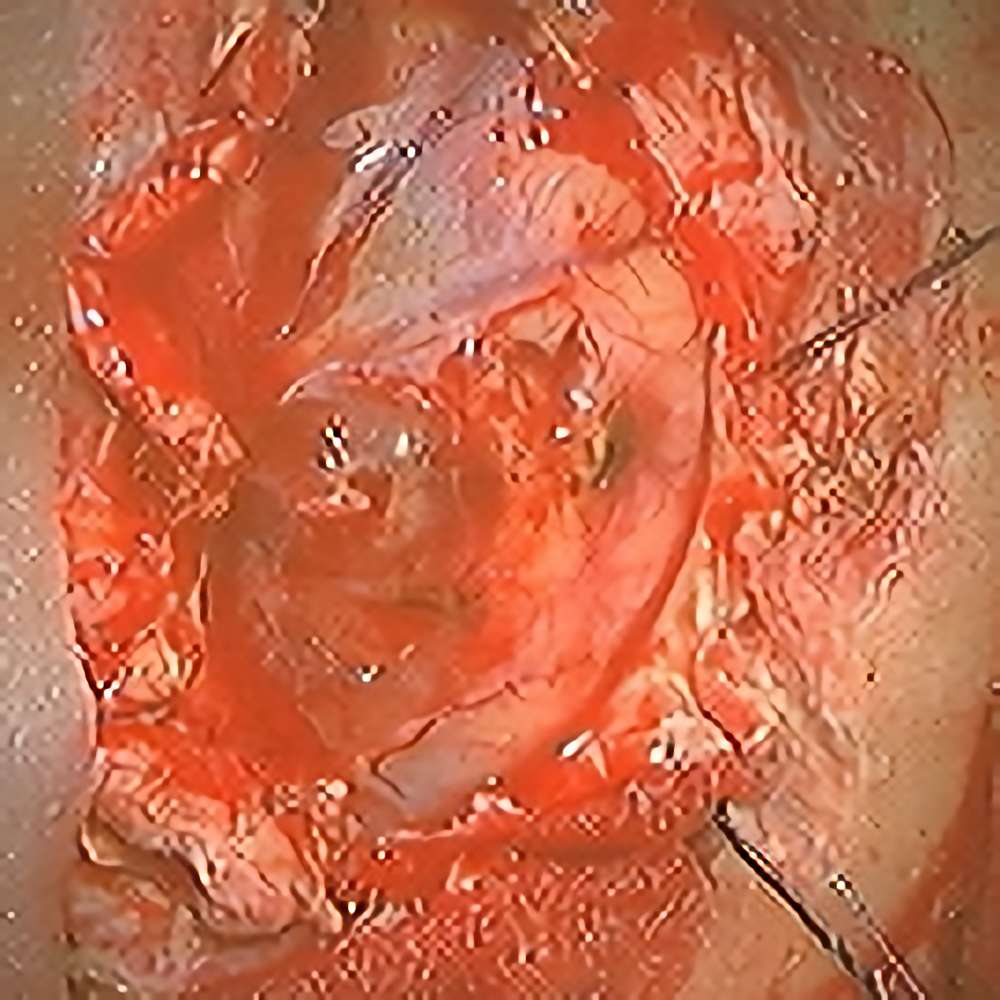

No.’21_27 摘出 前

No.’21_27  摘出 中

No.’21_27 摘出 後